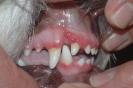

Rotes Zahnfleisch

(9 pictures)

Galerie rotes Zahnfleisch